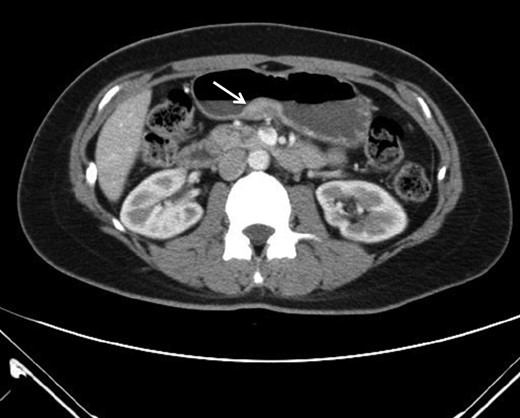

Heterotopic pancreas is a congenital anomaly with a reported prevalence of 0.5–13.7%. The most common locations are the upper gastrointestinal tract such as the stomach, duodenum and proximal jejunum. The less common sites are the esophagus, ileum and biliary tree. The diagnosis of heterotopic pancreas prior to surgery is difficult as it is generally asymptomatic. Besides, it also shares common features of the submucosal lesion under endoscopic (Fig. 4) or computed tomography examination. Although so, pathological changes similar to that of a normal pancreas (acute or chronic pancreatitis, cystic degeneration, malignant changes) are possible [4, 5]. Other than that, symptoms due to its anatomical position or tenderness resulting from the secretion of hormones and enzymes could all necessitate surgical interventions. By reviewing works of literature, we are able to gather some clues which might help us differentiate HP from other lesions before a treatment strategy is modulated. On conservative evaluations, a study conducted by Li et al. suggested that for masses <3 cm, a long diameter to short diameter ratio (LD/SD) greater than 1.29, enhancement value of >27.50 HU, enhancement ratio to pancreas of >0.72 are critical features [6]. Besides that, another study by Maryam et al. describes the MR imaging appearance of heterotopic pancreas mimics orthotopic pancreas. Characteristics of high signal intensity of the pancreas at T1-weighted imaging is useful for differentiation. Other than that, T2-weighted and MR cholangiopancreatographic images could help identify rudimentary or dilated ducts in the heterotopic pancreas to aid in differentiations [7]. Although endoscopic findings of central dimpling or umbilication which corresponds to an opening of a duct are the typical endoscopic finding for heterotopic pancreas, Haetaek et al. reported that it is seen in only 1/3 of cases. However, by using magnifying endoscopy with narrow band imaging, they can identify microscopic opening in more than 80% of lesions without a macroscopic opening, which suggests the possible usefulness of this method in predicting the diagnosis of heterotopic pancreas [8]. As for intervention approaches, endoscopic ultrasonographic fine needle aspiration (EUS-FNA) was reported to have a high sensitivity but somewhat limited diagnostic accuracy due to the limited quantity of tissue sample. A new technique of incorporating endoscopic submucosal dissection known as submucosal endoscopy with mucosal flap (SEMF) which could directly visualize the tumor or perform core biopsies has reported specific features of heterotopic pancreas as ‘yellow, cloudy, and soft with small nodule appearance similar to the pancreas.’ This endoscopic visualized features (EVF) could provide clues for the diagnosis of heterotopic pancreas. If uncertain, this technique could also provide the convenience of core biopsy samples for diagnosis prior to surgeries [3].

Gastrointestinal stromal tumor (GIST) under ultrasonography also shares similar feature by arising from the fourth layer of the gastric wall.